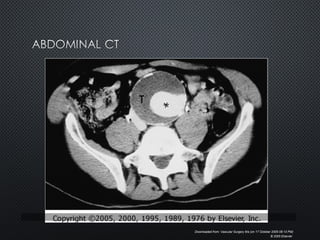

Downloaded from: Vascular Surgery 6/e (on 17 October 2005 11:17 PM)

© 2005 Elsevier